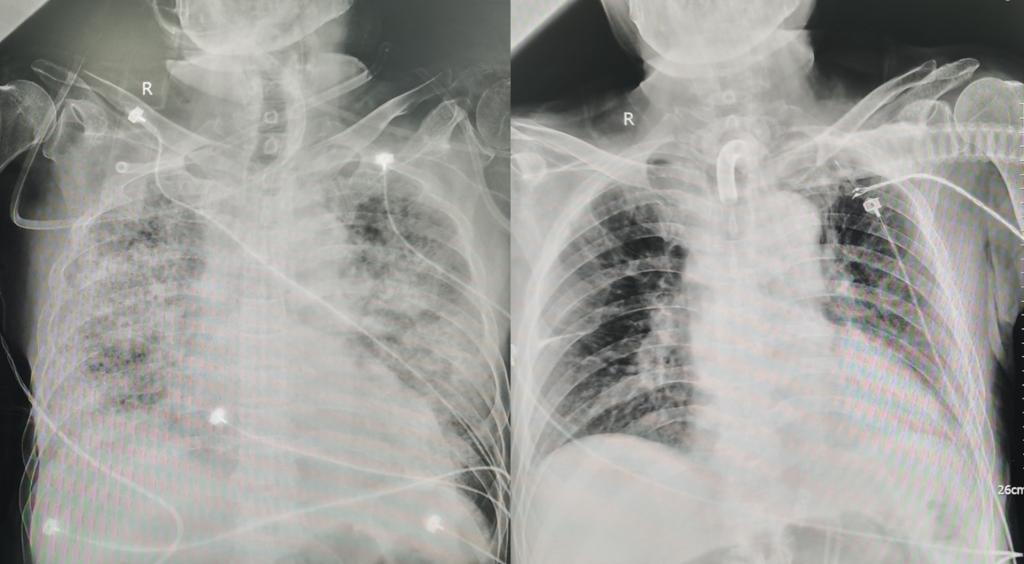

治疗期间影像学对比(左图为2023年10月5日,右图为2023年12月29日)

患者陈某,71岁,男性,因“咳嗽、发热、呼吸困难1周”于2023年09月26日入科。既往患高血压、高血压性心脏病、冠心病,曾行冠脉支架植入。患者于外院治疗期间肺部感染控制不佳,氧合状况进行性恶化,胸部影像迅速进为“白肺”,并肝功能不全,急诊转入呼吸与危重症医学科。入院后给予无创机械通气支持下床旁气管镜检查,肺泡灌洗液病原学检查明确诊断为嗜肺军团菌肺炎、ARDS。但患者对目标性治疗反应不佳,氧合状况持续恶化,2023年10月10日出现气胸,氧合指数降低至35.8mmHg,予以紧急气管插管,并行胸腔闭式引流术,患者氧合状况仍无改善,次日晨行VV-ECMO治疗。ECMO上机过程中,方萍教授带领团队成员认真分析病情,精心调整治疗方案,刘丽萍护士长带领ECMO专职护士精心护理,团队成员紧密协作,逐步解决了患者抗感染、出凝血平衡、肺外器官功能不全、胃肠功能、营养支持、内环境稳定等各个问题,患者病情逐步好转,于ECMO上机后第31天成功下机(单个膜肺连续使用31天),后续有创呼吸支持参数逐步下调,并积极予以康复功能锻炼。目前患者已顺利脱机拔管,可下床活动及经口进食,基本实现生活自理。